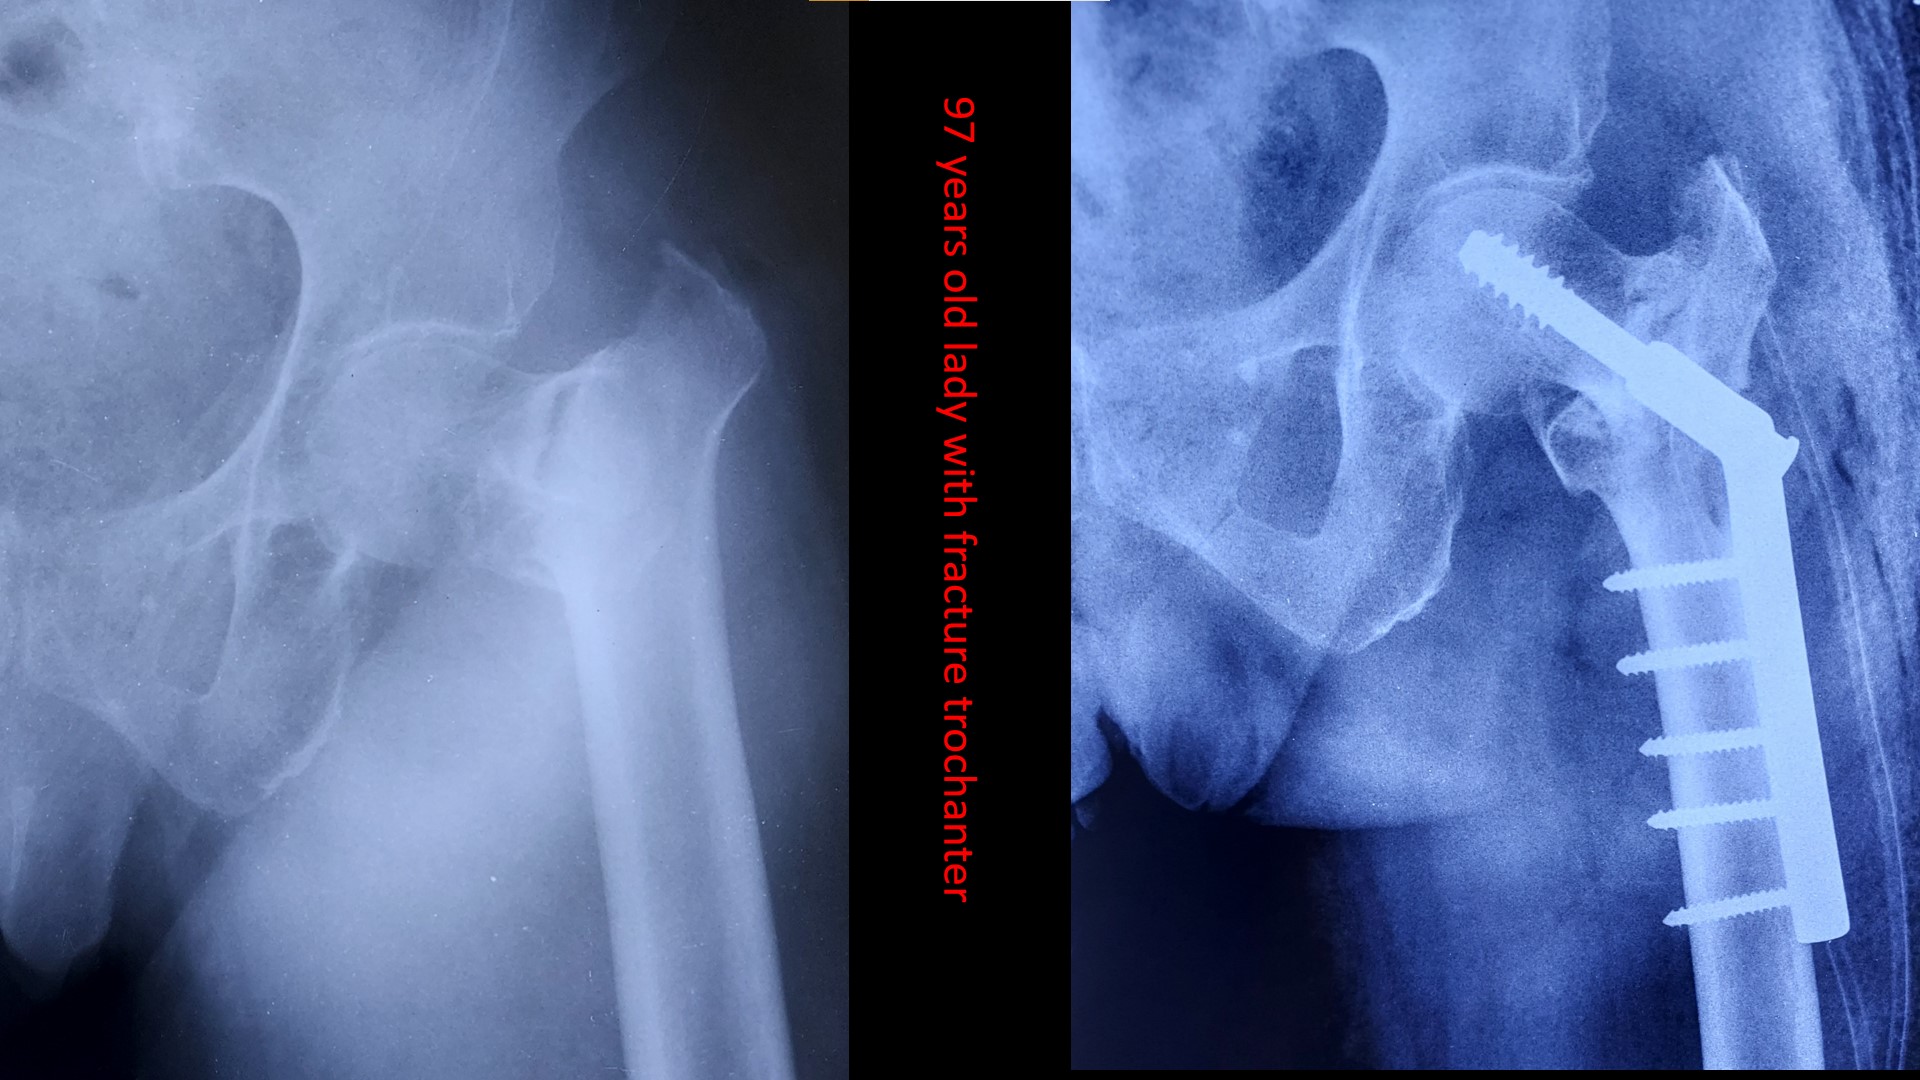

The care you deserve.

Please send us a message, or call us for an appointment. +919287283131,+9188166438,04662223131, 04662223785